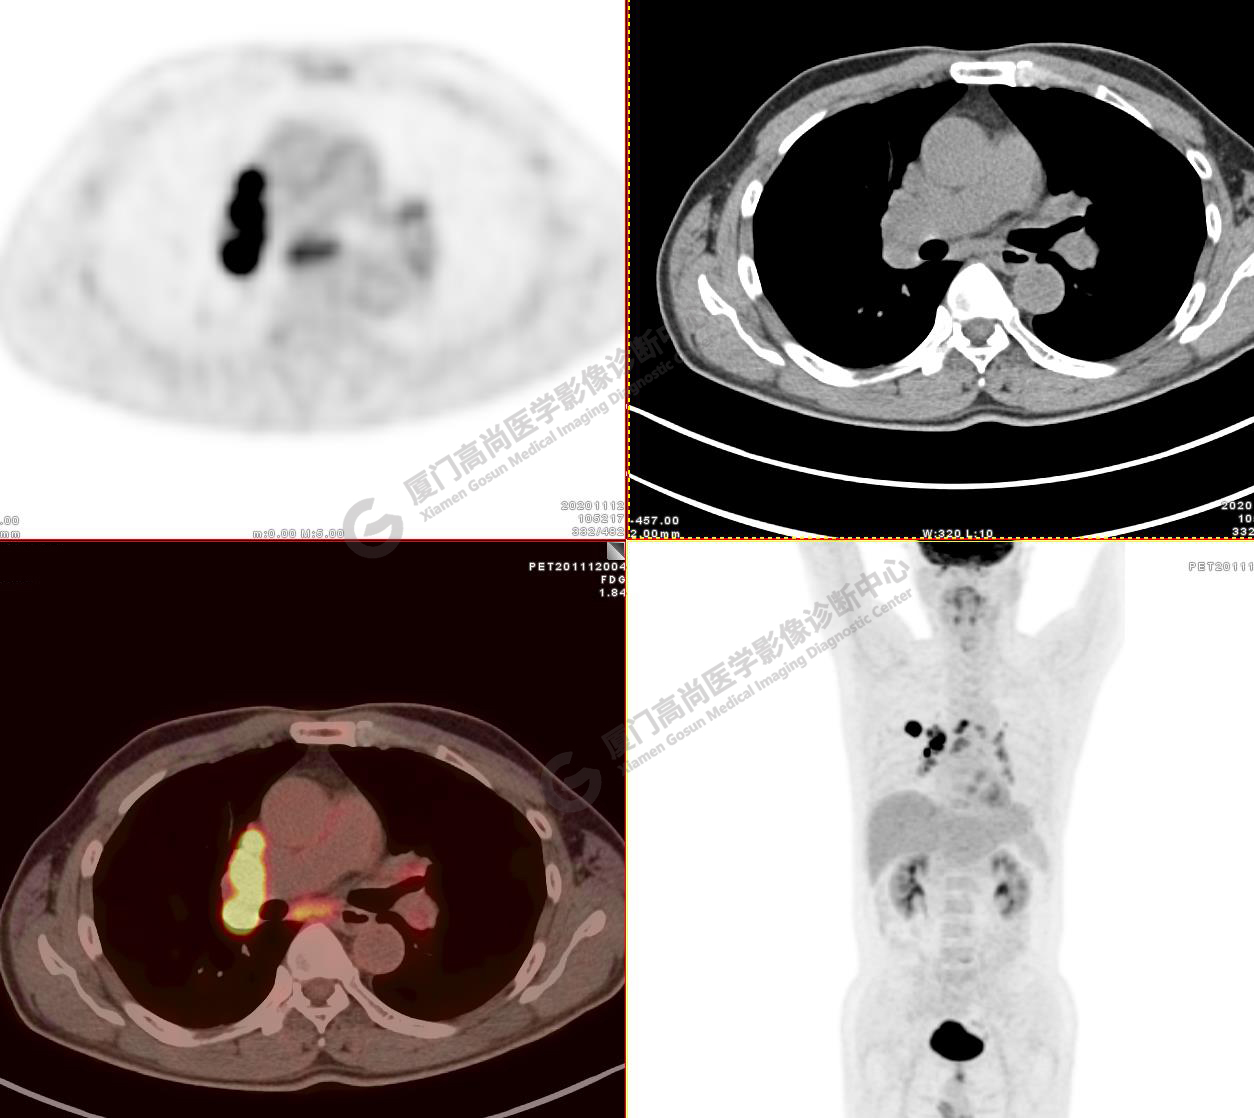

病例3:某女,47歲,咳嗽3周,無咯血,右上胸部疼痛,腰部疼痛

廈門市醫(yī)院查血腫瘤標記物,CA153、CA724、CA211、NSE、AFP、CEA、CA125均正常

右肺上葉前段實性腫塊,大小約3.2x2.7x2.6cm,邊緣見毛刺、分葉,胸膜牽拉明顯,前段支氣管阻塞。FDG攝取增高,SUVmax,16.8;右側(cè)頸部Ⅳ區(qū)、右側(cè)鎖骨區(qū)、右肺門及縱隔淋巴結(jié)腫大, FDG攝取增高,SUVmax7.9;C2、L2椎體、右側(cè)第6肋骨、骶骨、髂骨、左側(cè)髖臼、腰椎體及附件骨質(zhì)破壞,SUVmax11.8。

影像診斷:右肺上葉周圍型肺癌并多發(fā)淋巴結(jié)、骨骼轉(zhuǎn)移。(TNM分期,T2aN3M1c Ⅳ B期)

病理診斷:低分化腺癌